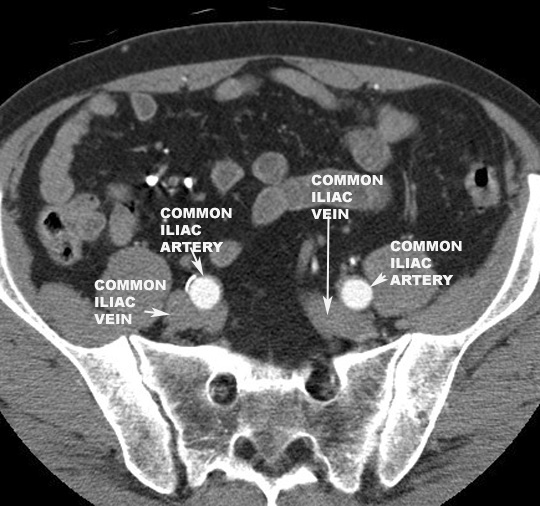

- Abdominal aorta ends by dividing at L4

into left and right common Iliac arteries

- About 4-5 cm in length

- Descends downward and outward toward the

edge of the pelvis.

- Travels

inferolaterally for approximately five cm and terminates

as the internal

and external iliac arteries at the level of the pelvic inlet (L5-S1).